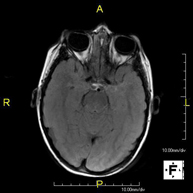

- RM Cerebral (cranial)

Prova diagnòstica no invasiva que consisteix en l'obtenció d'imatges d'alta definició anatòmica del cerbell mitjançant l'ús d'un camp electromagnètic i ones de ràdio (com un emissor i un receptor). No utilitza radiació ionitzant. Indicacions: problemes vasculars, pèrdua de memòria, epilèpsia, cefalea, malformacions, sospita de tumor, meningitis. - RM de Cais